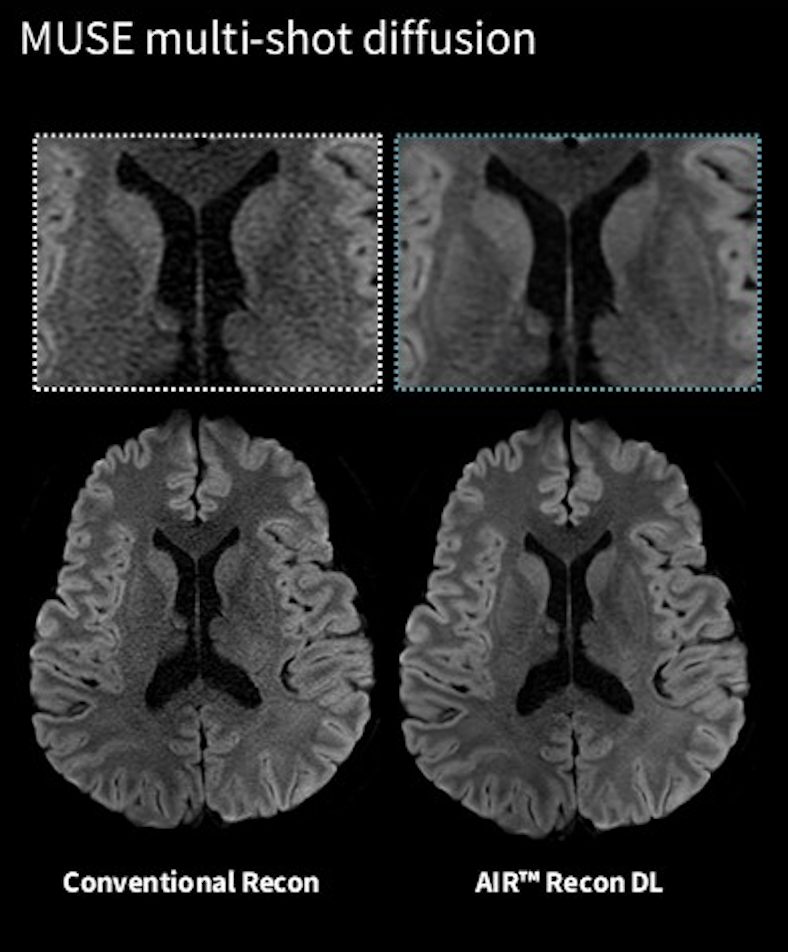

MUSE(multi shot DWI)でdeep learning技術が使用可能となりました。

これにより、multi shot DWIで画像歪みを抑制しつつ、SNRの担保をdeep learningで行えます。

Phase correctionを使用することで、AIR Recon DLだけでは除去できなかった位相エラー由来のノイズをさらに減少することができます。